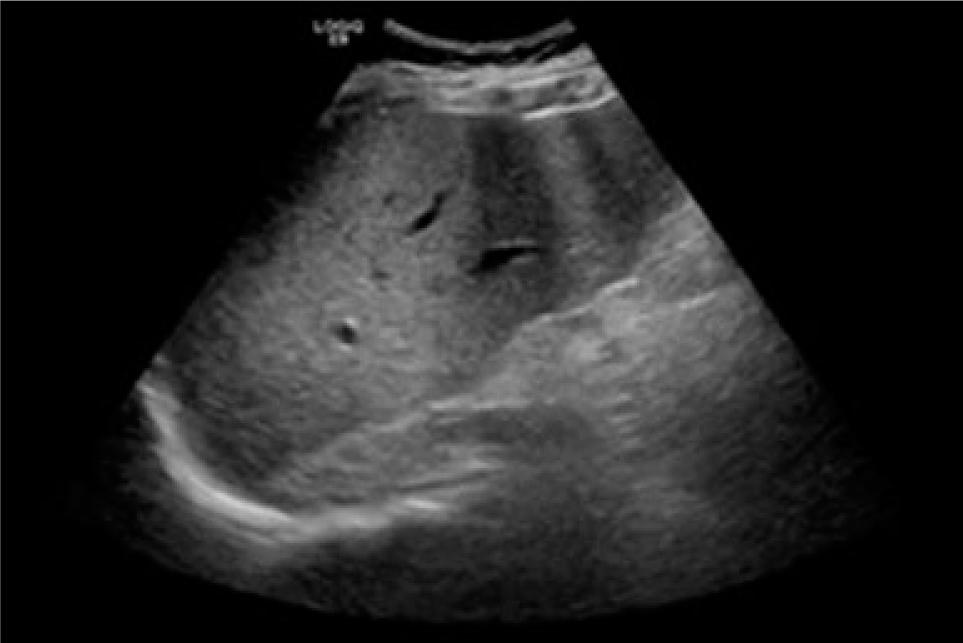

A 28-year-old man with no relevant family history presented with a history of living with multiple cats at home. He was diagnosed with a craniopharyngioma at the age of 15, underwent partial tumor resection in the same year; he also was diagnosed with type 2 diabetes at the age of 28, and experienced pulmonary thromboembolism at the age of 19 following a car accident with pelvic trauma. His body mass index was 34.6 kg/m2. During an endocrinology follow-up, the following laboratory results were reported: total bilirubin 3.15 mg/dL, direct bilirubin 1.22 mg/dL, indirect bilirubin 1.93 mg/dL, AST 60 U/L, ALT 41 U/L, gamma-glutamyl transferase (GGT) 84 U/L, alkaline phosphatase 146 U/L, hemoglobin 15.1 g/dL, and platelets 38,000 cells/mm3. Given a suspicion of hepatopathy, viral panel testing for hepatitis B virus, hepatitis C virus, and human immunodeficiency virus returned negative results. Autoimmune causes were also ruled out through serological tests. An abdominal ultrasound revealed grade 2 hepatic steatosis, splenomegaly, intrahepatic biliary duct dilation, and elastography indicating fibrosis (Figure 1). Ultrasound-guided biopsy showed characteristic changes of hepatic cirrhosis. The underlying cause of the hepatopathy was determined to be metabolism-associated fatty liver disease.

Figure 1: Abdominal ultrasound with findings consistent with chronic hepatopathy.